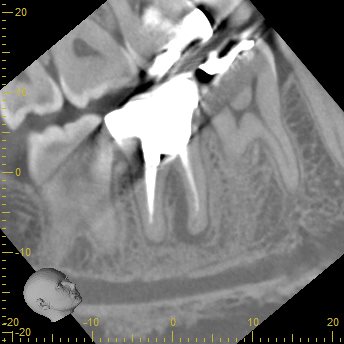

CBCT(2023.12.20)

MB

根切するには厳しい位置に#31のM根のApexはある。

穿通は必須である。

ML

MLには根尖病変と思しき透過像がそれほど顕著ではないが若干見える。

そして、生活歯髄療法の負の遺産がこの歯牙には発生している。

そう、

根管の石灰化

だ。

その歯に根尖病変ができている。

そして、Sinus tract。

この歯を根切することは容易であろうか?

といえば、

このCT画像が語っていることは、

頬側の皮質骨は相当厚いという臨床的事実だ。

それがApicoectomyを困難にしているのだろう。

できれば、非外科的な歯内療法でマネージメントしたい。

D

遠心根にはほぼ病変はないようだ。

ここは、再根管形成も不要と考えてもいいだろう。